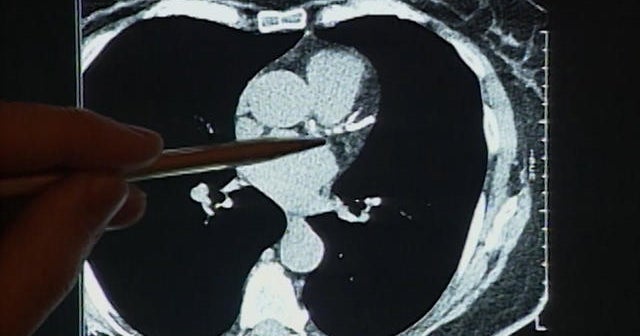

Heart disease deaths decline, but not equally

Deaths from heart disease have declined dramatically in recent decades, but a new study shows some groups have benefited more than others. Kenneth Craig reports.